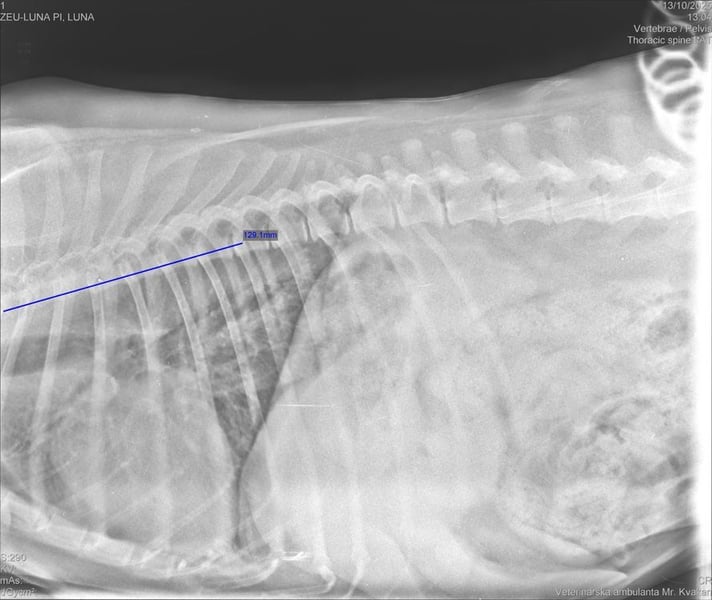

Mitte Oktober 2025 war die Tierheimleitung mit Pi zur vollständigen tierärztlichen Untersuchung in der Tierklinik. Dort wurde festgestellt, dass Pi an der Wirbelsäule Spondylose hat. Pi benötigt Schmerzmittel und zur Unterstützung der Gelenke Flexadin.

In der Bildergalerie befindet sich ein Röntgenbild von der Wirbelsäule. Weitere Röntgenbilder können Sie beim Vermittlungsgespräch von unseren Kontaktpersonen erhalten.